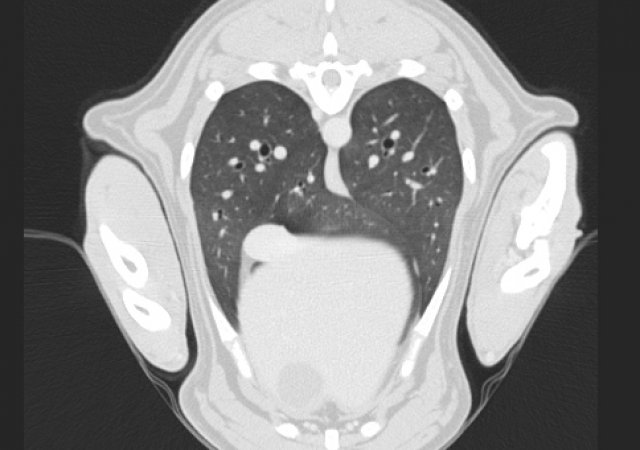

• Komplettes „Tumor Staging“ (Metastasensuche) mit CT der Lunge, Ultraschall des Bauchraums, Punktion von Lymphknoten oder von verdächtigen Umfangsvermehrungen